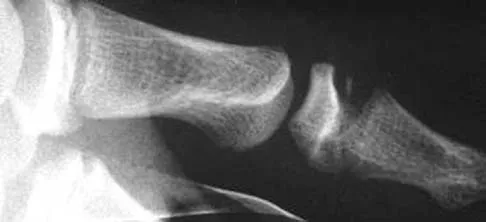

Figures 4a through 4c show the radiographs of a 43-year-old woman who sustained a twisting injury to her right ankle. She has ankle pain and tenderness medially and laterally. To help determine the optimal treatment, an external rotation stress radiograph of the ankle is obtained. This test is designed to evaluate the integrity of what structure?

Explanation

In the presence of a supination external rotation-type fracture of the distal fibula (Weber type B), stability of the ankle is best assessed by performing an external rotation stress AP view of the ankle. This test is used to assess the integrity of the deltoid ligament. The presence of a deltoid ligament rupture results in instability and generally is best managed surgically. The gravity stress test can also be used. Egol KA, Amirtharajah M, Tejwani NC, et al: Ankle stress test for predicting the need for surgical fixation of isolated fibular fractures. J Bone Joint Surg Am 2004;86:2393-2398. McConnell T, Creevy W, Tornetta P III: Stress examination of supination external rotation-type fibular fractures. J Bone Joint Surg Am 2004;86:2171-2178.